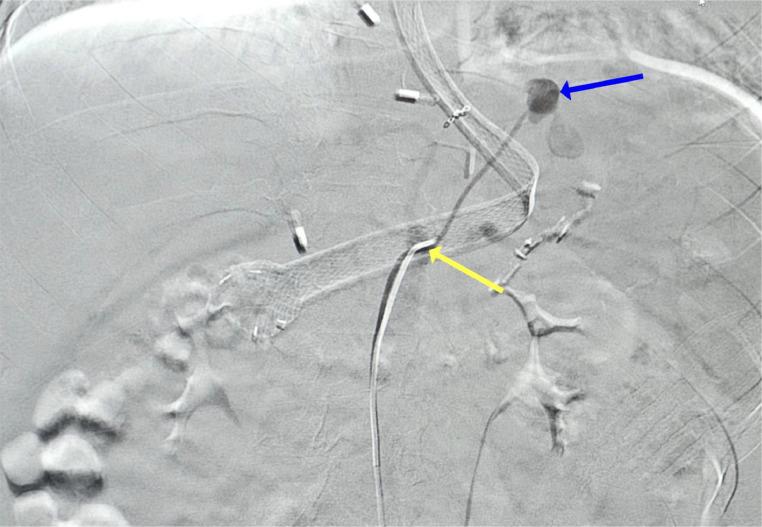

血管内栓塞术成功治疗术后左膈动脉假性动脉瘤所致胃出血:一例报告

Successful treatment of gastric bleeding caused by left phrenic artery pseudoaneurysm post-surgery with endovascular embolization: A case report.

Pseudoaneurysms are rare but potentially life-threatening complications that may occur after surgical procedures. This report presents the case of a 28-year-old woman who developed a pseudoaneurysm in the Left Inferior Phrenic Artery (LIPA) following a Laparoscopic Sleeve Gastrectomy (LSG). The complication manifested as severe gastrointestinal bleeding. Upper GI Endoscopy and multislice CT scan, repeated twice, failed to localize the bleeding source to treat it. Successful endovascular embolization using a Glue/Lipidol mixture was achieved despite difficulties in localizing the pseudoaneurysm, resulting in immediate symptomatic relief and avoiding surgical intervention. This case shows the importance of prompt identification and management of LIPA pseudoaneurysms following LSG, highlighting the importance of early diagnosis to prevent further hemodynamic deterioration and other adverse outcomes.

摘要